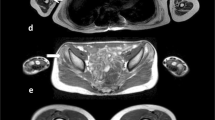

In 102 patients (21 immune-mediated necrotizing myopathy/IMNM, 21 inclusion body myositis/IBM, 10 GNE myopathy/GNEM, 19 Duchenne muscular dystrophy/DMD, 12 dysferlinopathy/DYSF, 7 limb-girdle muscular dystrophy/LGMD2I, 7 Pompe disease, 5 spinal muscular atrophy/SMA), two MRI scans were obtained at a 1-year interval in thighs and lower legs. Regions of interest (ROIs) were drawn in individual muscles, muscle groups, and the global muscle segment. Standardized response means (SRMs) were determined to assess sensitivity to change in fat fraction (ΔFat%) in individual muscles, muscle groups, weighted combinations of muscles and muscle groups, and in the global muscle segment.

Global muscle segmentation gave high SRMs for ΔFat% in thigh and lower leg for IMNM, DYSF, LGMD2I, DMD, SMA, and Pompe disease, and only in lower leg for GNEM and thigh for IBM.

Global muscle segment Fat% showed to be sensitive to change in most investigated neuromuscular disorders. As compared to individual muscle drawing, it is a faster and an easier approach to assess disease progression. The use of individual muscle ROIs, however, is still of interest for exploring selective muscle involvement.